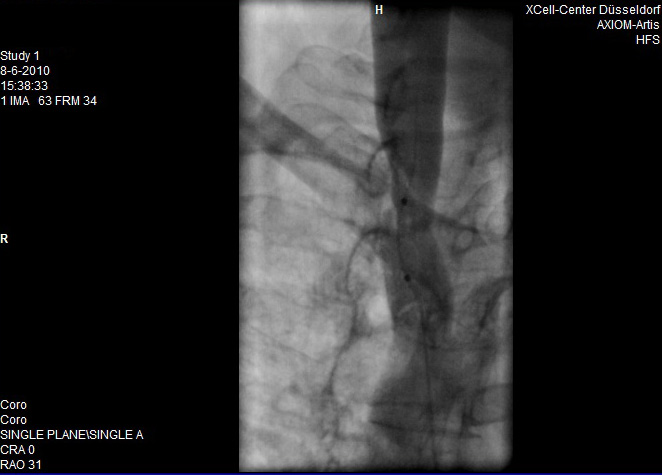

En hier de scans van de behandeling

Opmerkingen bij bestand: Dit is de balooning

tijdensballoon.jpg

tijdensballoon.jpg [ 50.8 KiB | 19706 keer bekeken ]

Wat ik kon zien was dat de stenose als je het in % kan uitdrukken op zo'n 40% kleiner dan "normaal" was.

Hierop heeft hij gebalooned (12 atmosfeer) .

Dit heeft hij een aantal malen gedaan waarbij het resultaat op de monitor iets meer verwijding was wat mij verbaasde.